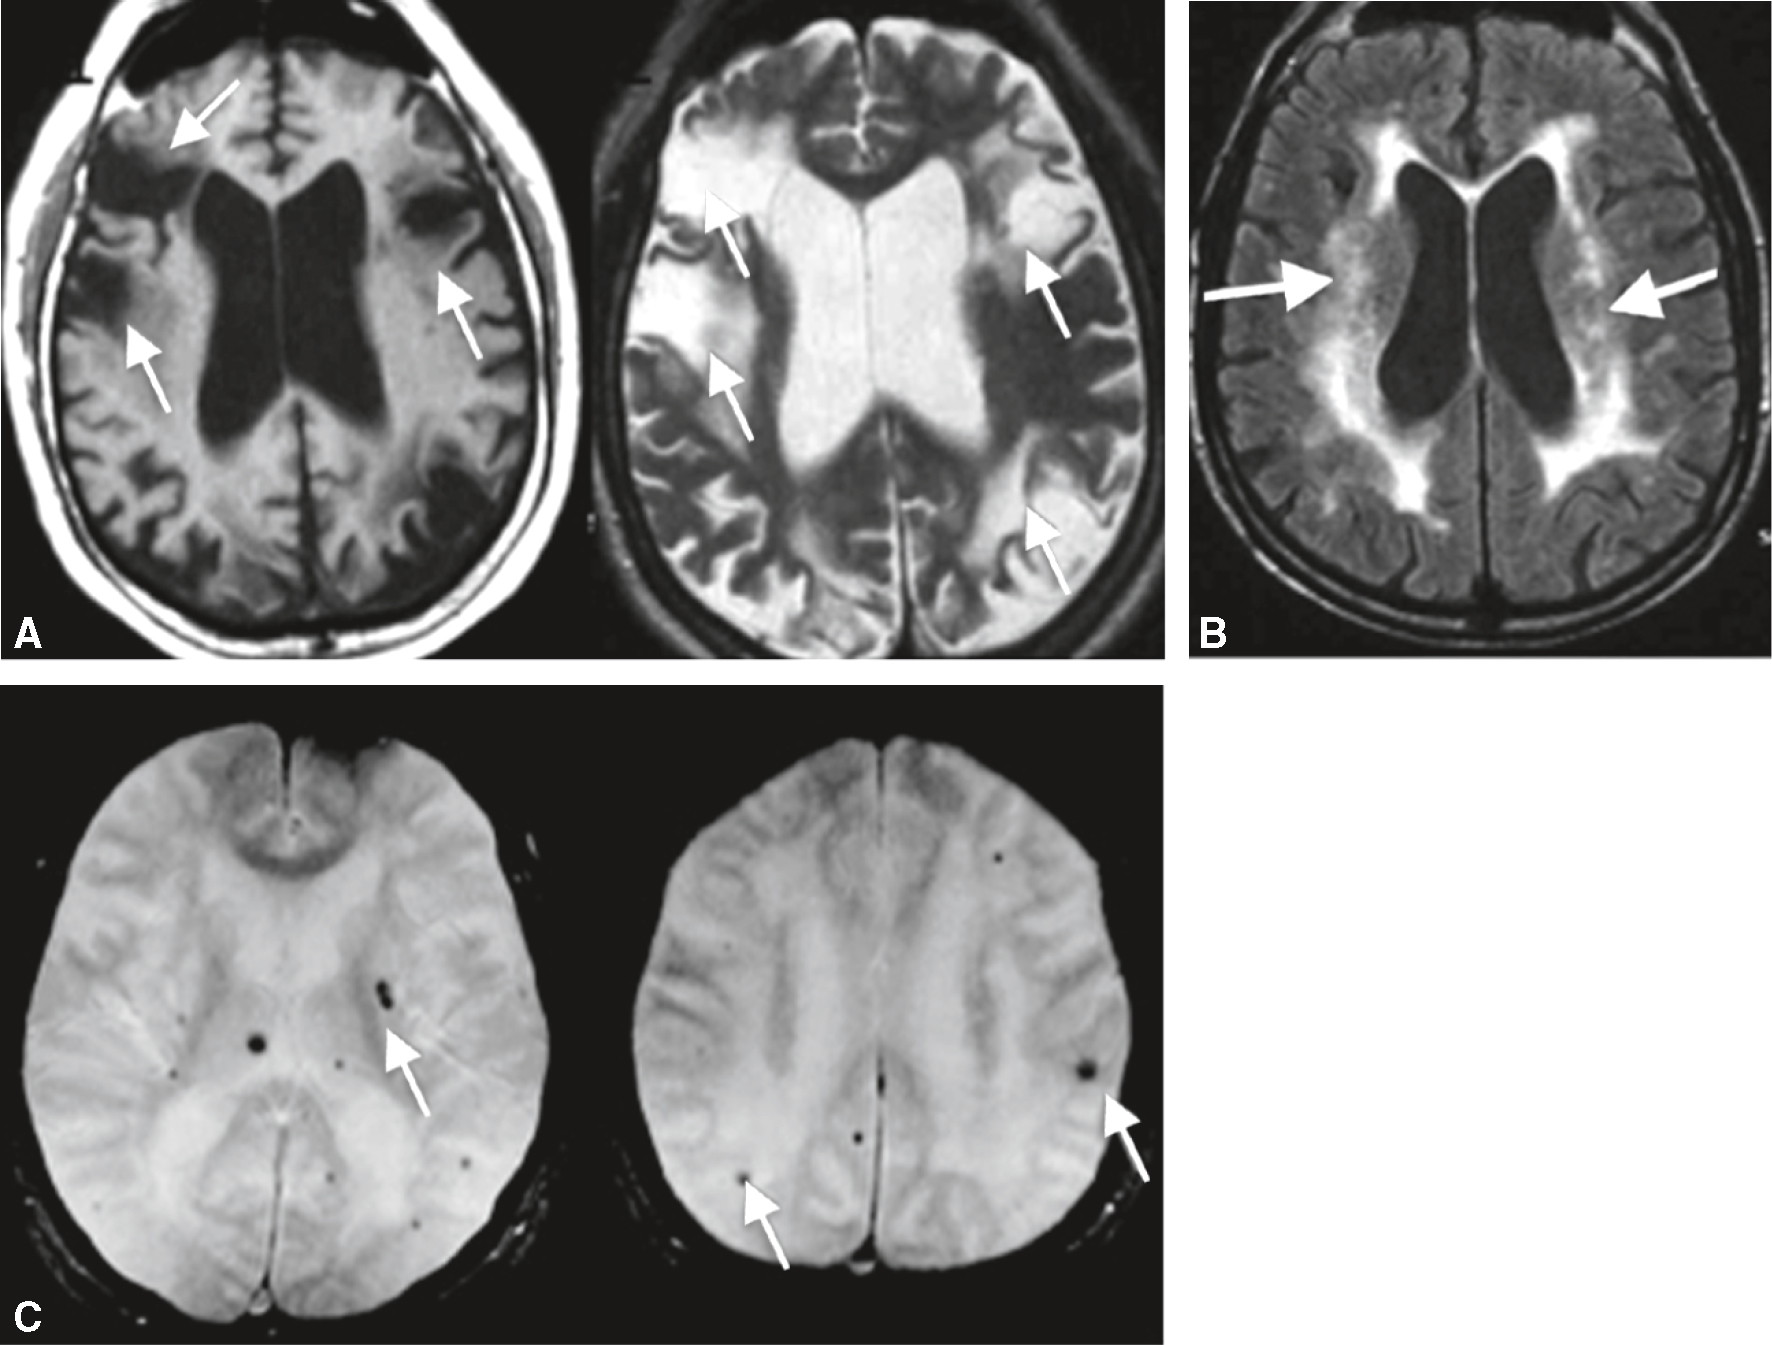

- • détecter des lésions vasculaires ischémiques et hémorragiques (séquences utiles : T2/FLAIR et T2 en écho de gradient, respectivement);

Fig. 22.7

Exemples en IRM de lésions vasculaires responsables de troubles cognitifs et de démences.

A. Infarctus corticaux et sous-corticaux multiples (séquences T1 et T2). B. Hypersignaux de la substance blanche sus-tentorielle (séquence T2/FLAIR). C. Microsaignements (séquence T2, écho de gradient).L'image présente des exemples de lésions vasculaires cérébrales observées par IRM, responsables de troubles cognitifs et de démences. L'image A montre des coupes axiales du cerveau avec des flèches indiquant des zones de lésions vasculaires. Ces lésions apparaissent sous forme de zones hyperintenses, plus brillantes que le tissu cérébral environnant, souvent associées à des dommages aux petits vaisseaux sanguins, entraînant des troubles cognitifs. L'image B montre aussi une coupe axiale du cerveau avec des flèches pointant vers des lésions hyperintenses autour des ventricules cérébraux, les cavités remplies de liquide céphalorachidien. Ces lésions périventriculaires, courantes chez les personnes âgées, peuvent indiquer une leucoaraïose, liée à des troubles cognitifs et à la démence. L'image C présente deux coupes axiales du cerveau avec des flèches indiquant des microhémorragies cérébrales, des taches sombres représentant des saignements microscopiques, souvent causés par une hypertension chronique ou d'autres maladies vasculaires. Les microhémorragies peuvent contribuer aux troubles cognitifs et à la démence en endommageant le tissu cérébral. Ces images sont importantes car elles illustrent les différents types de lésions vasculaires pouvant affecter le cerveau et entraîner des troubles cognitifs et des démences. Elles montrent comment l'IRM peut être utilisée pour détecter et évaluer ces lésions, fournissant des informations cruciales pour le diagnostic et la gestion des troubles cognitifs.

- • 406Les lésions vasculaires par atteintes des petites artères (HTA, diabète) comprennent les lacunes, les hypersignaux de la substance blanche, les microsaignements et les petits infarctus sous-corticaux. Leur sommation peut aboutir à un TNC ou à une démence dite « vas-culaire » d’apparition insidieuse. La maladie des petites artères est souvent associée à une atteinte neurodégénérative de type Alzheimer, une situation appelée TNC ou démence mixte.